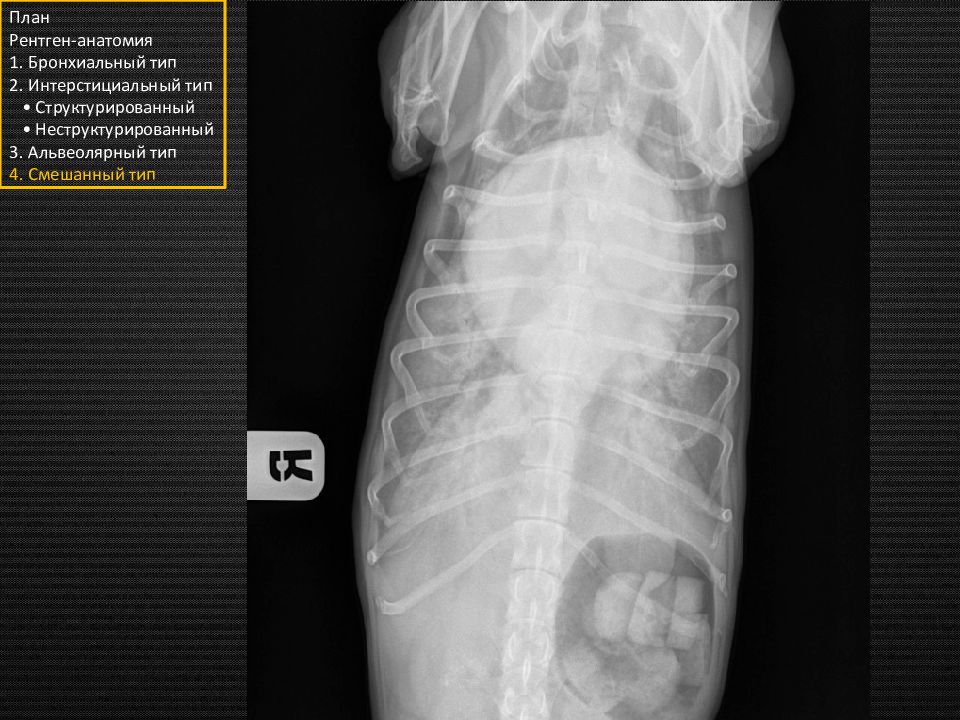

Слайд 7

Кошка. Норма. План Рентген-анатомия 1. Бронхиальный тип 2. Интерстициальный тип • Структурированный • Неструктурированный 3. Альвеолярный тип 4. Смешанный тип